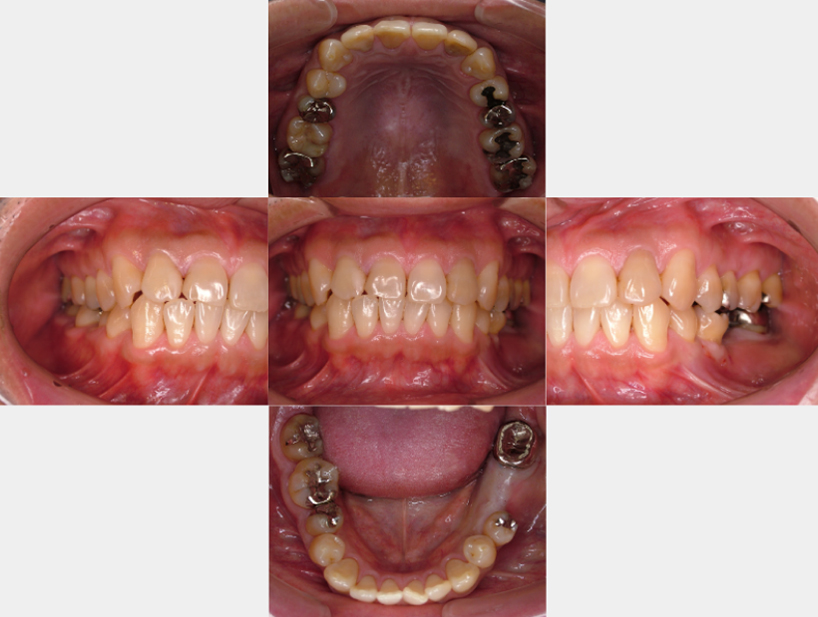

治療前治療後

| 治療内容 | インプラント奥歯1本・根管治療6歯 |

|---|---|

| 患者様の年齢 | 54歳 |

| 患者様の性別 | 女性 |

| 治療期間 | 2年 |

| 治療回数 | 根管治療合わせて70回程度 |

| 治療費用 | インプラント1歯 50万円/根管治療6歯 30万円 |

| 治療で得られるメリット |

|

| 治療する際に起こる リスク・副作用 |